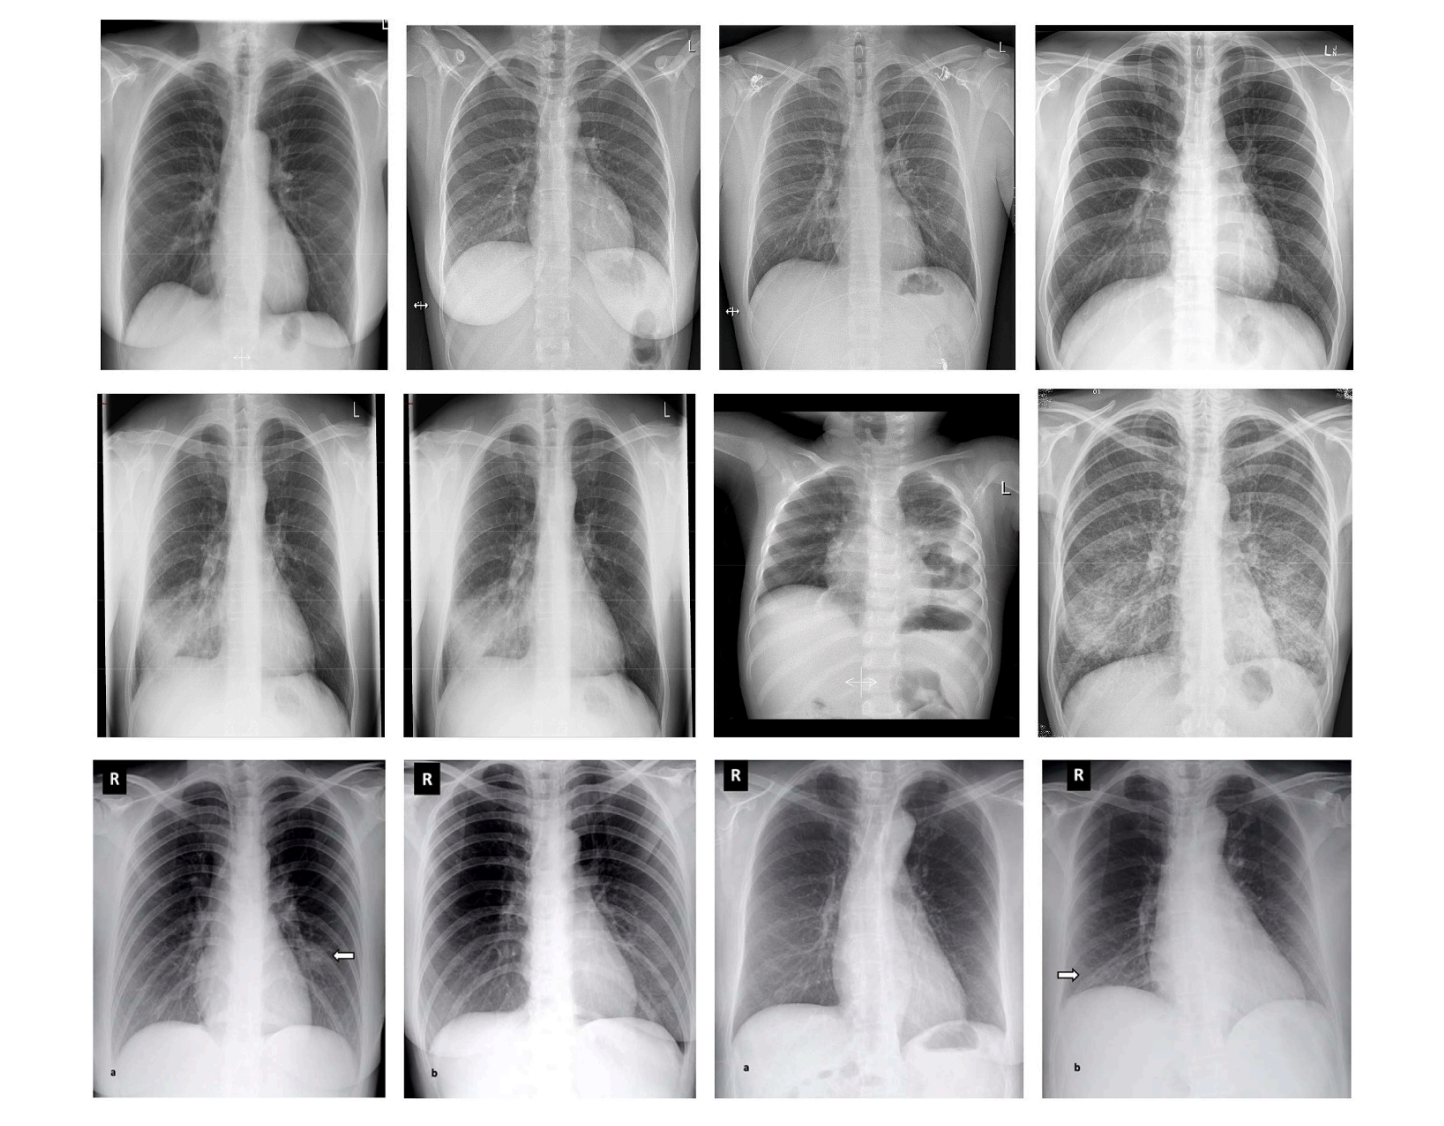

Figure 2. Sample images from each class. The paper shows example X-rays for COVID-19, Pneumonia, and Normal categories. :